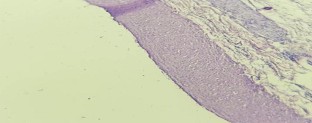

Fig. 1